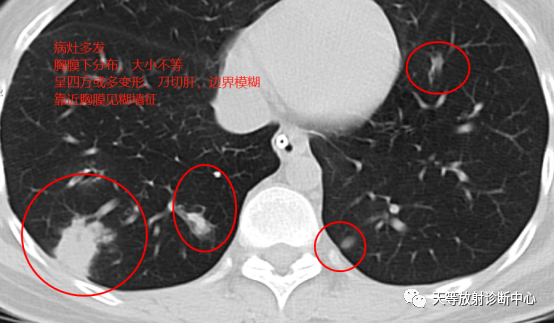

影像学表现:整体观察肺内多发病灶,散在分布,病灶的主要形态为:多发大小不等肺气囊、多发结节共同存在。

4、结节影大小不等,小的呈树芽征堆积,大的部分到达胸膜小,具有糊墙征,性格较温和。仔细观察病灶呈四边形、多边形,边缘刀切感,边界模糊。

首先感觉病变并不是非常的恶,偏向温和的病变。